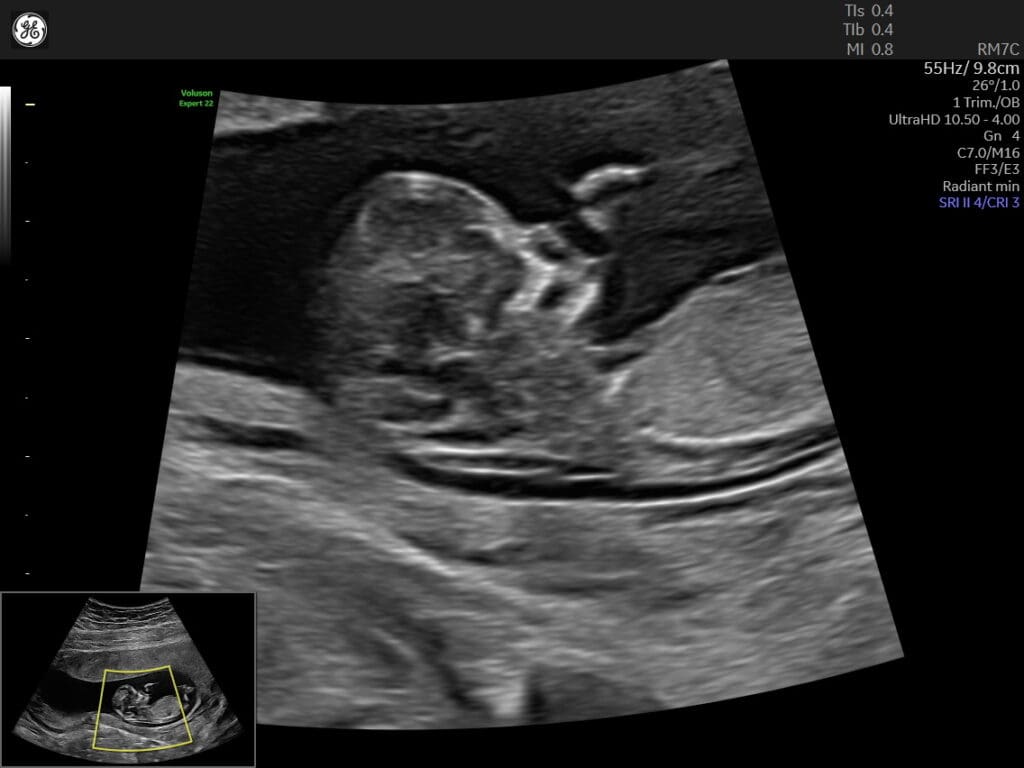

The NT scan is performed through an ultrasound examination, where the technician measures the clear space, called the nuchal translucency, that is visible at the back of the baby’s neck. The measurement is usually done while the baby is in a specific position, allowing for accurate assessment.

The purpose of the NT scan is to assess the risk of chromosomal abnormalities, particularly Down syndrome (Trisomy 21) and other genetic conditions. An increased nuchal translucency measurement may indicate an elevated risk, while a normal measurement provides reassurance but does not rule out the possibility of chromosomal abnormalities.